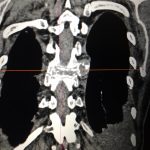

Εικόνα 1: Αξονική Τομογραφία (30.10.2018) Θωρακικής Μοίρας Σπονδυλικής Στήλης (ΘΜΣΣ)

(α,β) Οβελιαία Λήψη Παρατηρείται καταστροφή του Σπονδυλικού σώματος και η κυφωτική γωνίωση της Σπονδυλικής Στήλης. Προβολή προς τα πίσω μάζας, αποτελούμενη από οστικά στοιχεία και ράκη του Μεσοσπονδυλίου Δίσκου, η οποία ασκεί πρόσθια πίεση επί του Νωτιαίου Μυελού.

(γ,δ) Εγκάρσια Λήψη Παρατηρείται καταστροφή του Σπονδυλικού Σώματος, αμφοτερόπλευρη προσβολή των πλευραγκαρσίων αρθρώσεων και είσοδος μαζών, προσθίως μέσα στο Σπονδυλικό Σωλήνα.

(ε,στ) Μετωπιαία Λήψη Παρατηρείται η καταστροφή του σπονδυλικού σώματος του 8ου Θωρακικού σπονδύλου, αμφότερα επέκταση νεοπλασματικών μαζών, και κατεστραμμένα σπονδυλικά στοιχεία.